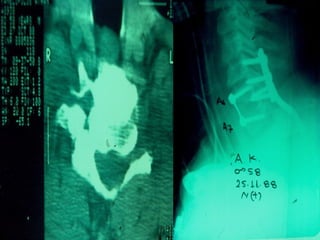

Injuries of tthhee uuppppeerr cceerrvviiccaall ssppiinnee

PCR

SUMMIT

Μετεγχειρητικές ακτινογραφίες – 18mts